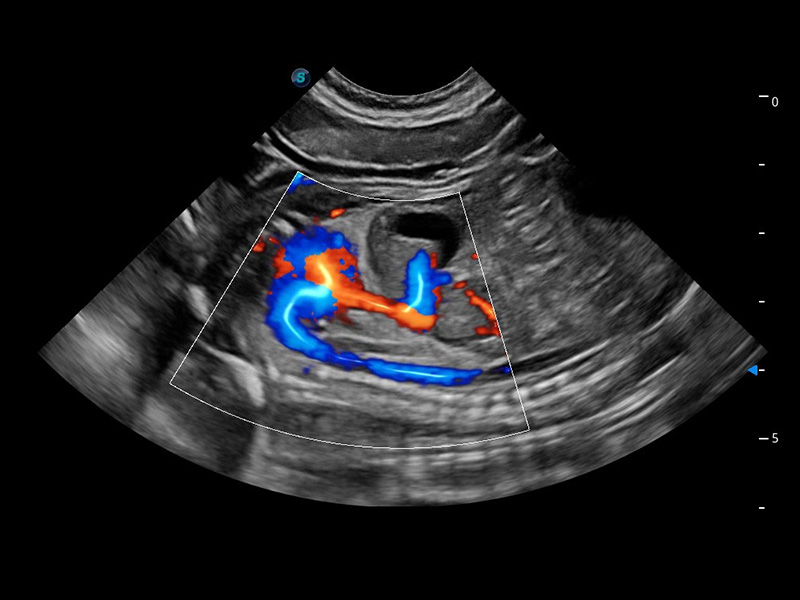

ProPet 60 作为一款高端台式动物超声设备,为动物医生的日常诊断提供了一系列贴合动物临床需求、解决临床实际问题的高级成像功能。凭借全系列高清探头,满足医生对腹部、心脏、生殖、浅表、肌骨等成像的所有需求,切实帮助您提升检查效率,提高诊断信心。

兽用彩色多普勒超声诊断系统

动物是人类最亲密的朋友和最值得信赖的伙伴。玖鼎集团也一直致力于探索动物专用的超声影像解决方案。 全新推出的ProPet系列,是玖鼎集团在动物超声影像智能化、专业化、精准化的一次跨越式革新。动物不能用言语来表述自己的不适,通过超声影像,ProPet系列搭建了动物医生与不同物种沟通的“桥梁”,为动物医生注入了“治愈之力”。